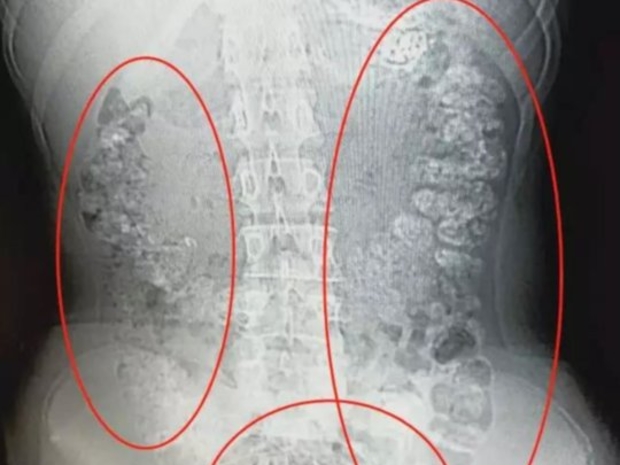

تسبب إدمان مراهقة صينية على مشروب الشاي باللبن المثلج، في إصابتها بإمساك على مدى خمسة أيام، أدى إلى حدوث كارثة غير متوقعة. وعندما ذهبت الفتاة إلى المستشفى، عثر الأطباء على أكثر من 100 كرة تابيوكا صغيرة في جسم المراهقة الصينية، التي أدمنت تناول المشروب الآسيوي الشهير، والذي يُدعى شاي الفقاعة.

ونقلت الفتاة إلى المستشفى من قبل والديها في شرق الصين، بعد إصابتها بإمساك على مدى خمسة أيام. وقال الأطباء إن أمعاء الفتاة شياو شين فشلت في هضم كرات التابيوكا التي تصاحب هذا الشاي.